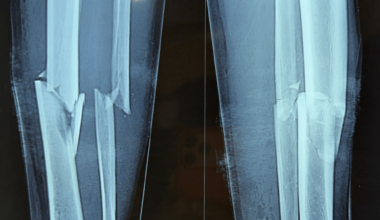

Successful Management of a Gustilo-Anderson Type I Open Comminuted Tibial Fracture Using Ilizarov Circular External Fixation: A Case Report